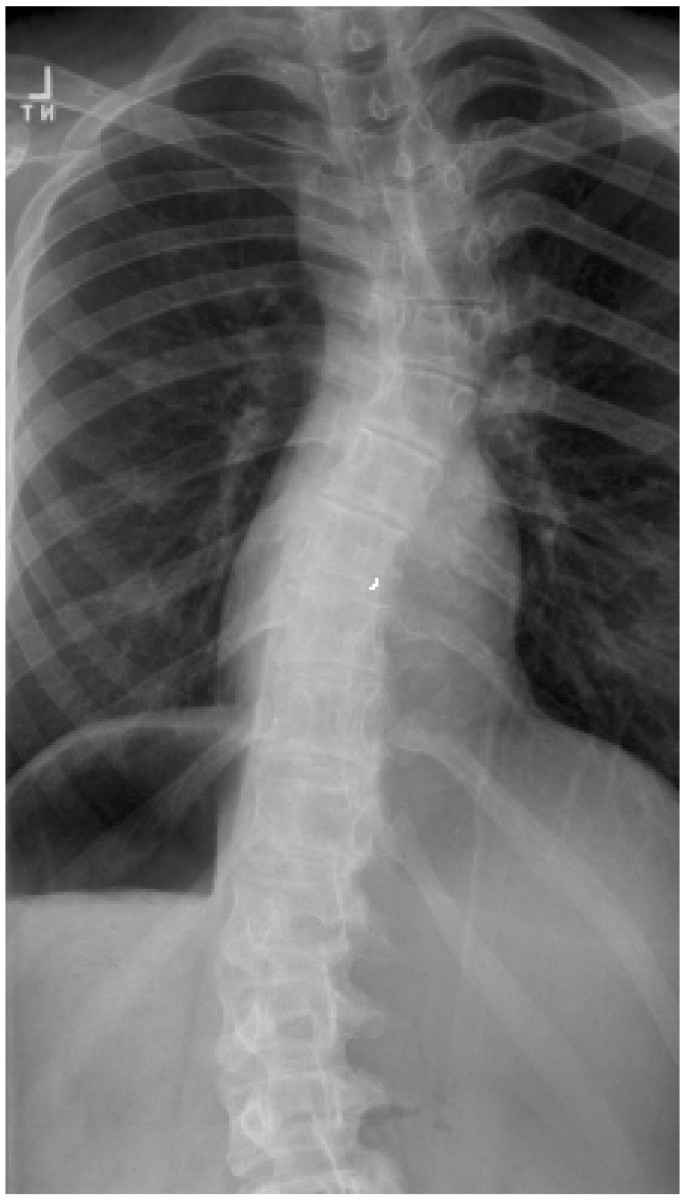

Radiologic confirmation of the spine deformity

Spine radiographs of all patients with clinical signs of scoliosis have been performed with the exception of one with Turner syndrome and another who had undergone deep Xray therapy. Both were skeletally mature at the time of clinical examination. Standard postero-anterior and lateral complete spine radiographs in the erect posture were reviewed. Images at the time of clinical examination were in a hard-copy form and images after 2002 were in digital format. Cobb angles were drawn by the treating scoliosis surgeons and recorded.

Turner syndrome subgroup

Of 45 with Turner syndrome, one had congenital scoliosis and underwent scoliosis surgery at age 13. Curve progression was not recorded for this patient. Thirteen of the 45 (28.8%) had scoliosis radiologically indistinguishable from idiopathic scoliosis (Figures 1, 2, 3). The mean age at diagnosis of scoliosis was 13 (range 3–22 years). All had oestrogen supplementation for delayed puberty. The site/morphology of the scoliosis and karyotype was recorded (Table 3). One had scoliosis prior to the commencement of HGH treatment and two others were diagnosed with scoliosis within one year of commencing the HGH treatment programme. The deformity subsequently progressed in both, resulting in right thoracic curves of 45°. Another underwent surgery for the scoliosis deformity, during HGH treatment. Analysis of the Turner syndrome subgroup revealed that they were administered a larger average dose of growth hormone (milligrams per kilogram body weight) (p = 0.003) and were commenced on the OZGROW program at an earlier age (p < 0.001) than the group comprising idiopathic short stature. The magnitude of the scoliosis curve in Turner syndrome was not influenced by the duration of HGH therapy.